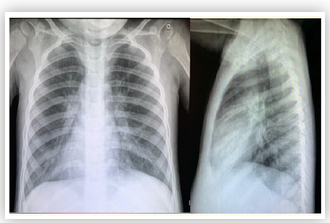

Tuberculosis Revealing Niemann Pick Disease Type B in a Teenager

Amal Ouayad, Karima Elfakiri, Noureddine Rada, Ghizlane Draiss, Naima Fdil and Mohammed Bouskraoui.